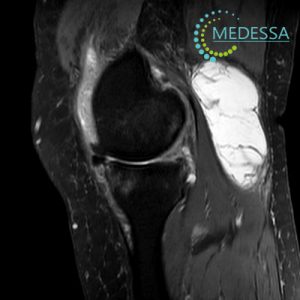

МРТ колінного суглоба – Кіста Бейкера або бурсит Бейкера

Кіста Бейкера, також відома як кіста синовіальної оболонки або бурсит Бекера, є аномалією, пов’язаною з суглобом, найчастіше з колінним суглобом. Ця кіста формується внаслідок накопичення суглобової рідини в задній частині коліна, утворюючи мішок або кісту.

МРТ надає докладні зображення м’яких тканин, кісток та суглобів, що дозволяє лікарям побачити структурні зміни в колінному суглобі, включаючи кісти, пошкодження хряща, запалення та інші аномалії.

МРТ може допомогти у точній локалізації та визначенні розмірів кісти. Це важливо задля розробки ефективного плану лікування.

МРТ може надати інформацію про те, наскільки сильно кіста впливає на навколишні тканини, такі як м’язи, сухожилля та інші структури. Це важливо при виборі методу лікування.